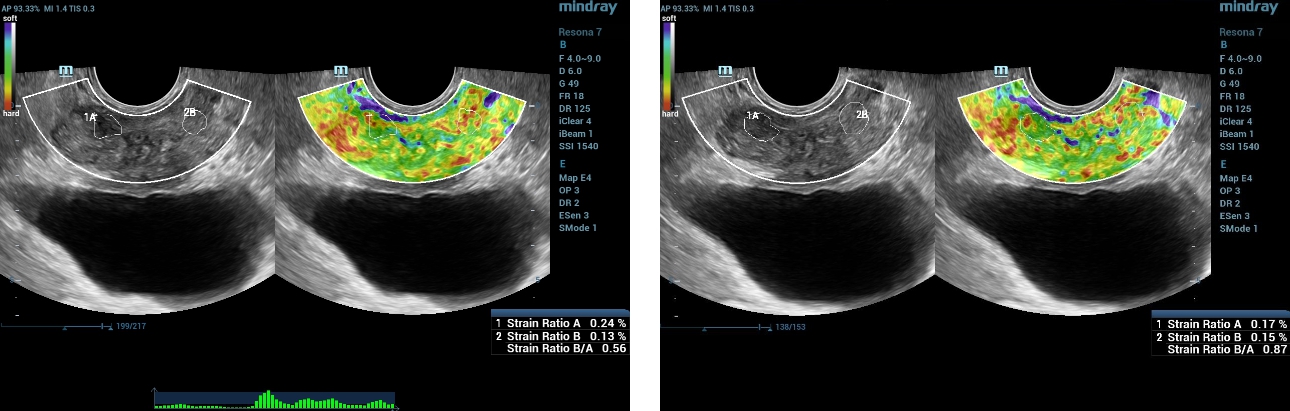

Strain Elastography Findings

Using Natural Touch Elastography on the Resona 7 the stiffness of the prostate gland was assessed. The hypoechoic lesion within the peripheral zone did not show as significantly stiffer than the surrounding tissue with a Strain Ratio measuring between 0.56-0.87.